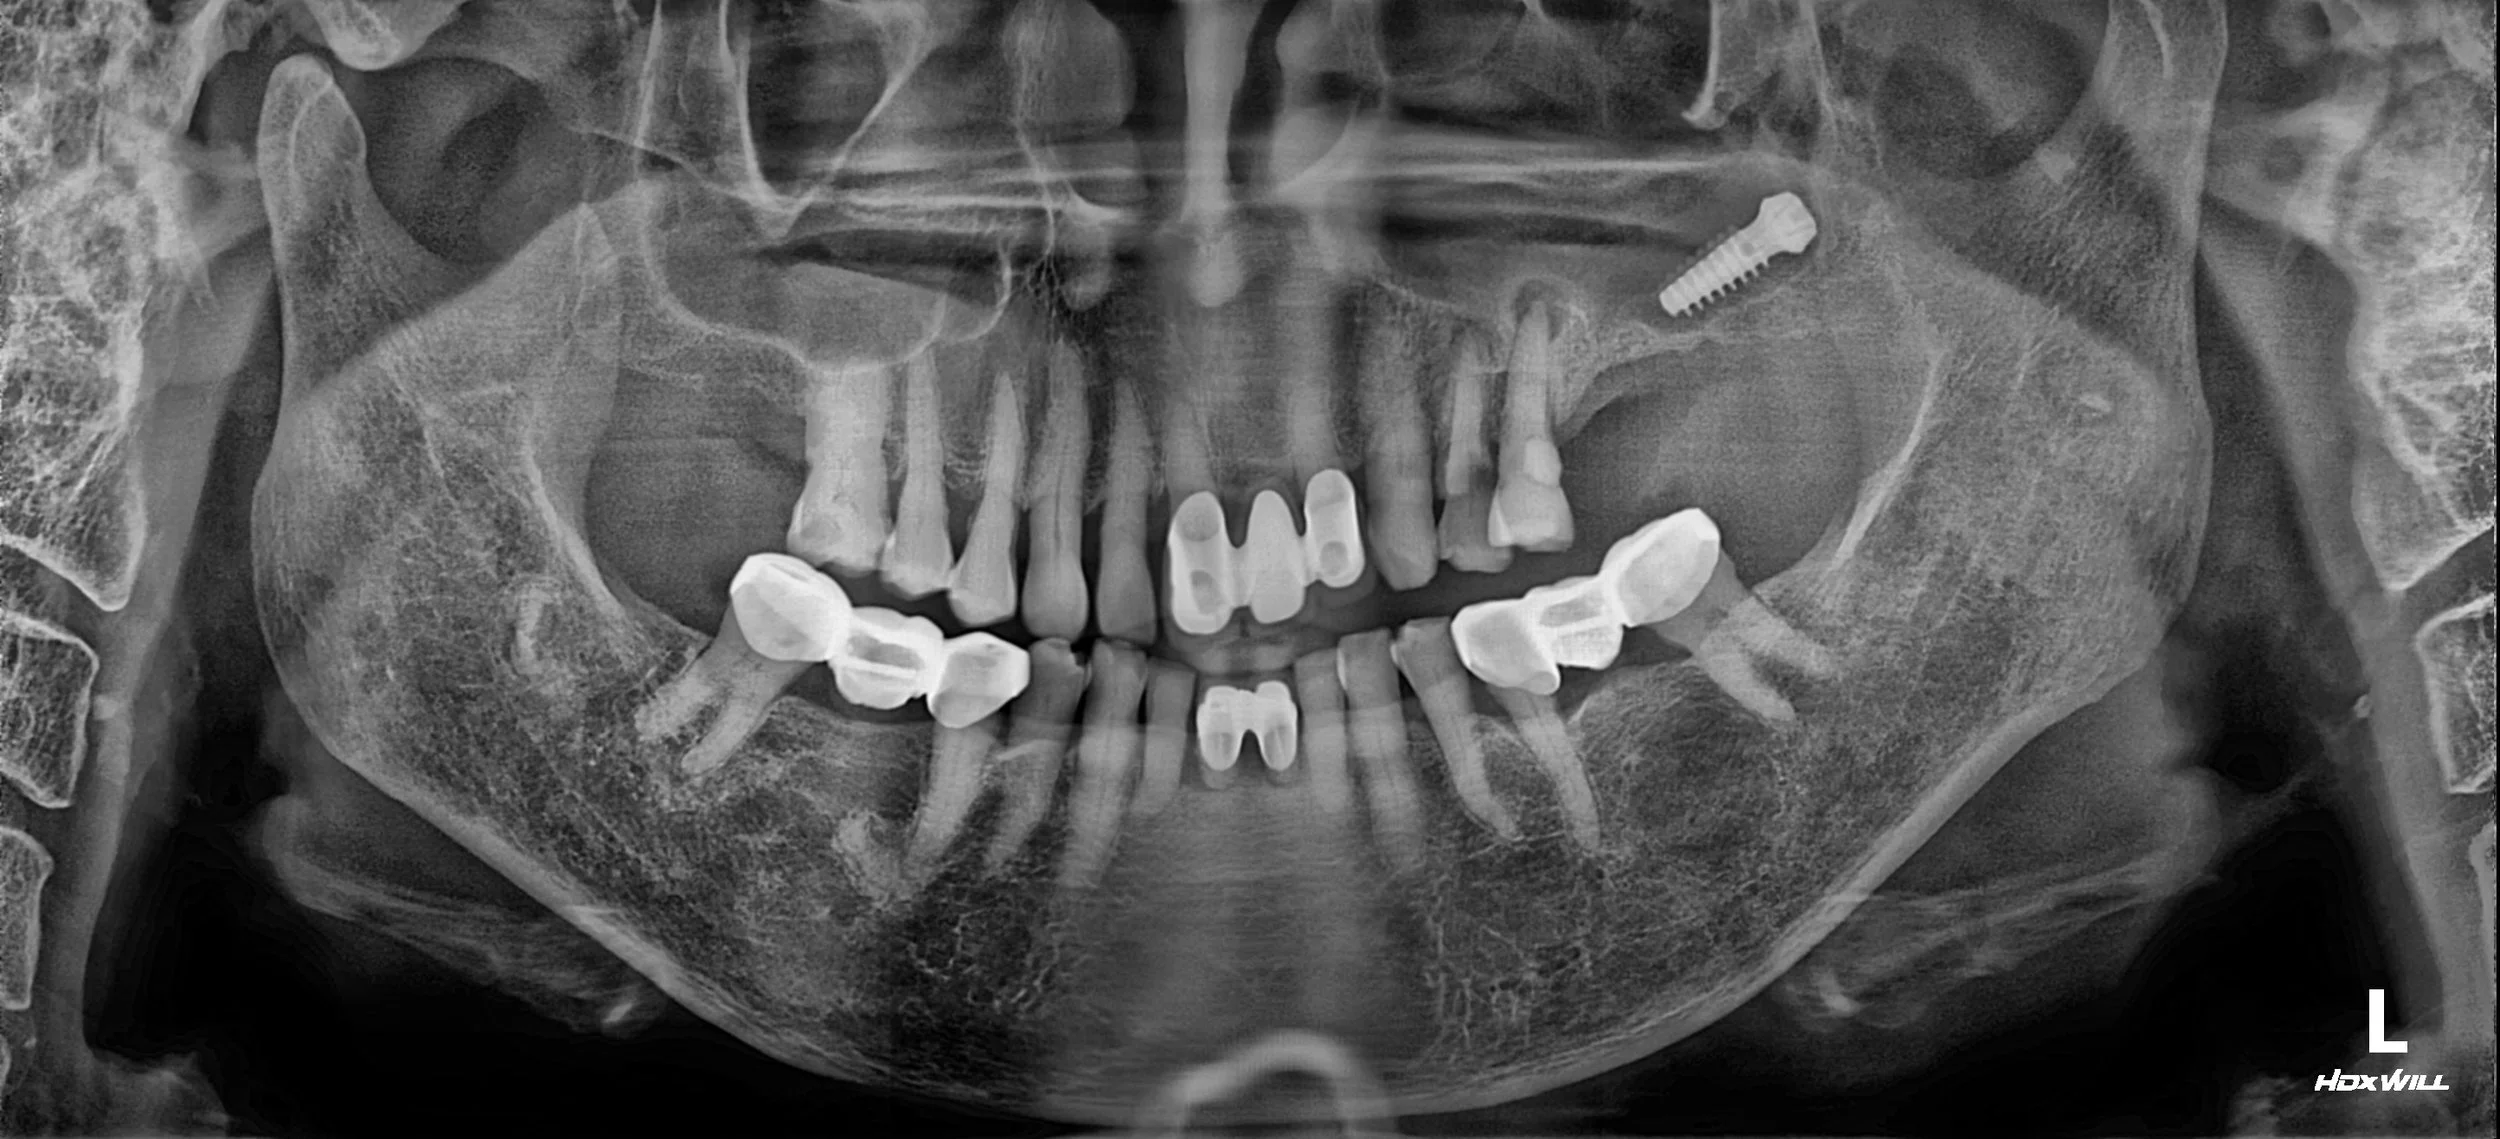

The patient presented with long-standing occlusal instability following a failed implant treatment several years prior.

A displaced implant fixture was identified within the maxillary sinus, accompanied by chronic maxillary sinusitis originating from residual teeth with advanced apical pathology.

Prolonged unilateral mastication had resulted in progressive occlusal imbalance, multiple tooth fractures, and symptoms suggestive of temporomandibular joint dysfunction.

OPG - BEFORE